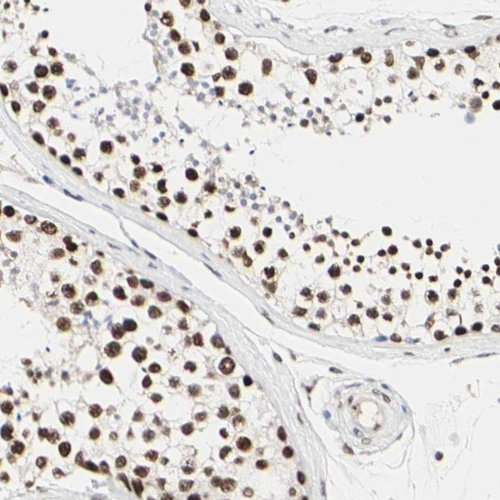

Immunohistochemical staining of human testis shows nuclear positivity in cells in seminiferous ducts.